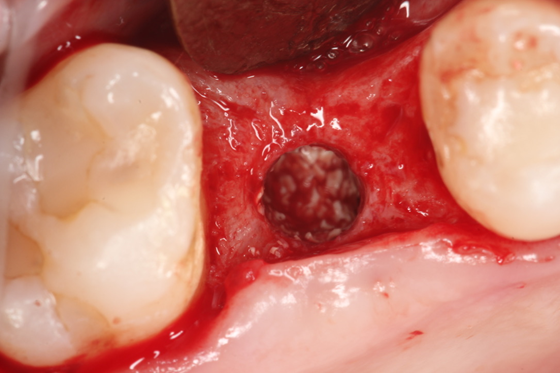

Paciente C.B.F.J., 33 anos, leucoderma, não-fumante e em boas condições de saúde sistêmica, relatou sensibilidade dolorosa durante mastigação no elemento 26, que já possuía tratamento endodôntico, pinos metálicos intrarradiculares e coroa metalocerâmica (Figura 1). Foi solicitada tomografia computadorizada de feixe cônico, na qual a imagem sugeriu fratura radicular na região da furca, descontinuidade óssea da cortical de seio maxilar e opacificação parcial do seio maxilar esquerdo (Figura 2). Foi realizada a exodontia e pôde-se confirmar a comunicação oroantral (Figura 3). Após curetagem do alvéolo, sem preocupação em curetar e remover a lesão cística sinusal, uma barreira reabsorvível foi recortada e posicionada no fundo do alvéolo para obliterar a descontinuidade óssea e impedir que células de tecido mole oriundas da cavidade sinusal invadissem a região alveolar (Figura 4). O alvéolo foi preenchido totalmente por coágulo sanguíneo do paciente (Figura 5) e o alvéolo foi selado por uma barreira não-reabsorvível (Figura 6), impedindo a invasão de fibroblastos do tecido gengival para dentro do alvéolo. Após duas semanas, a barreira estava estável e, então, foi removida, desnudando um tecido de granulação osteoblastogênico (Figura 7).